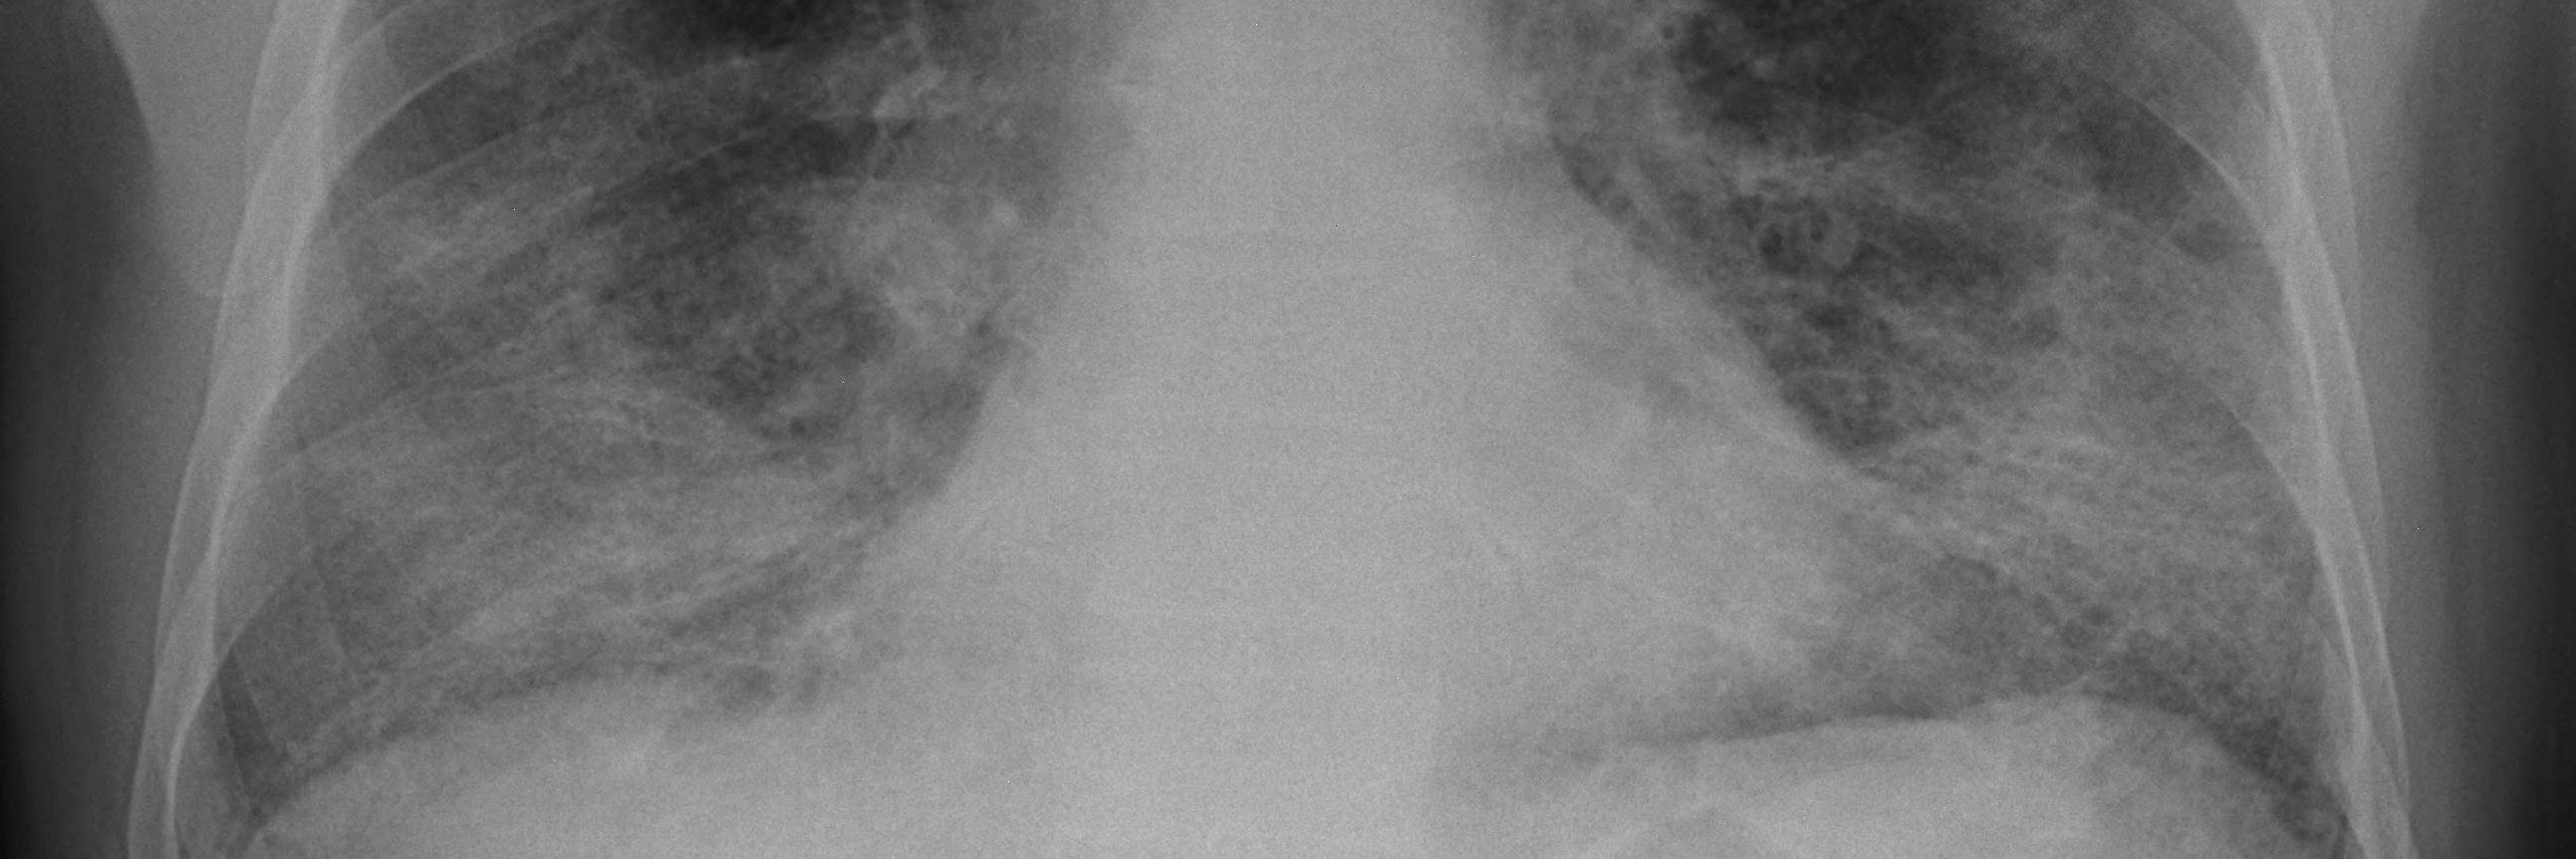

We are pleased to share the positive topline results from the Phase 2b CORAL Trial of Haduvio in Patients with Idiopathic Pulmonary Fibrosis Chronic Cough. Join our conference call today, June 2nd, at 8:30 a.m. ET. Read the press release: ow.ly/MCzh50W2spG $TRVI

Presented at #ATS2025: In the FIBRONEER-IPF phase 3 trial, nerandomilast slowed disease progression in patients with idiopathic pulmonary fibrosis as compared with placebo. Full trial results: nej.md/4mgWcIU @atscommunity